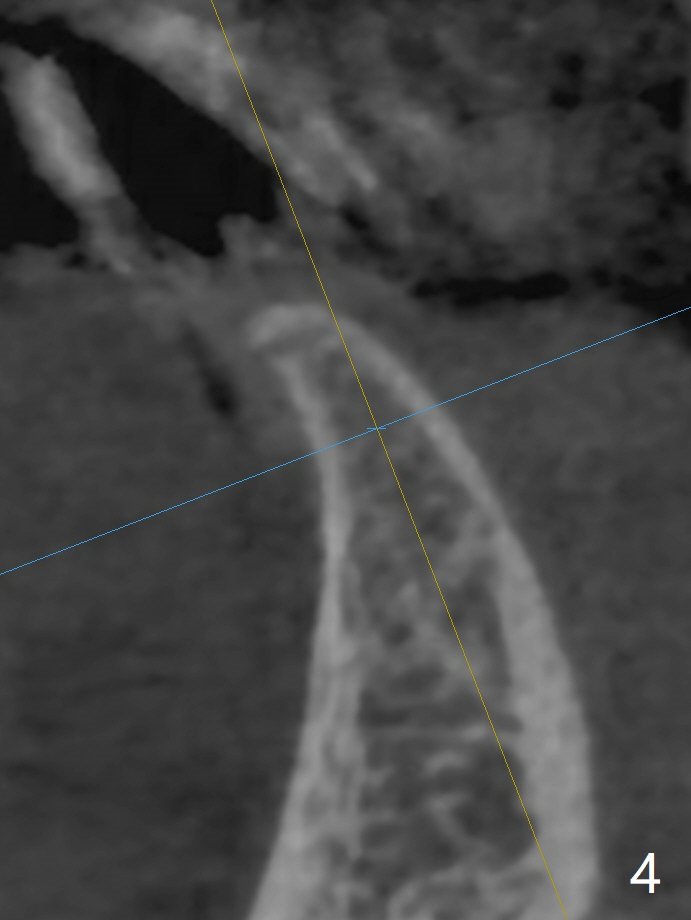

可以重做下颌7个连体牙冠,连接所有牙冠,中缝不再出现,但是费用高,口腔卫生不容易维持。简易办法是种植一个连体植体(1 -piece implant, 2.5x12(4) mm (直径,长度(袖),图二,图三(冠状截面))。 切口暴露狭窄牙槽嵴(图四),截除牙槽顶(图五黑色),然后在平坦骨面开始钻洞(图六红色箭头)。植体尽量种深点防止螺纹暴露,后期骨质密度容易增加。第一个钻头1.5x10毫米,拍摄根尖片,如果方位好,使用2x12mm, 2.5x6 mm钻头,或者2.5mm tap,植体植入。如果方位不好,纠正后,一定要有根尖片证实,才能用下一个钻头。牙槽嵴截除处骨质密度~700单位(图七),不是很高,放置植体前不必用同等大小钻头或者tap。